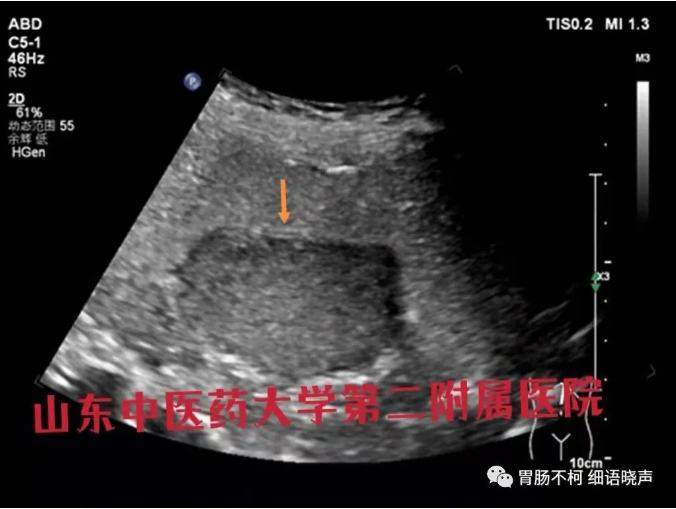

病例二,超声胃壁七层不显示、只显示五层时,自黏膜上皮线起始至肿块,胃壁五层显示了强(L1)-低(L2)-强(L3-5)三层线,强烈提示肿块跟L6(固有肌层)关系密切,结合混杂回声特点,诊断为间质瘤: